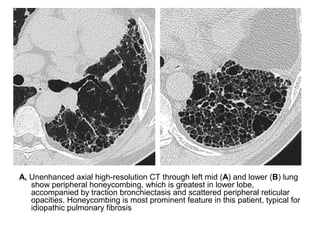

Honeycombing & traction bronchiectasis in UIP

Honeycombing comprises reticular densities caused by the thick walls of the cysts.

Whenever you see a chest film with long standing reticulation with a lower lobe and

peripheral preference

A, Unenhanced axial high-resolution CT through left mid (A) and lower (B) lung

show peripheral honeycombing, which is greatest in lower lobe,

accompanied by traction bronchiectasis and scattered peripheral reticular

opacities. Honeycombing is most prominent feature in this patient, typical for

idiopathic pulmonary fibrosis